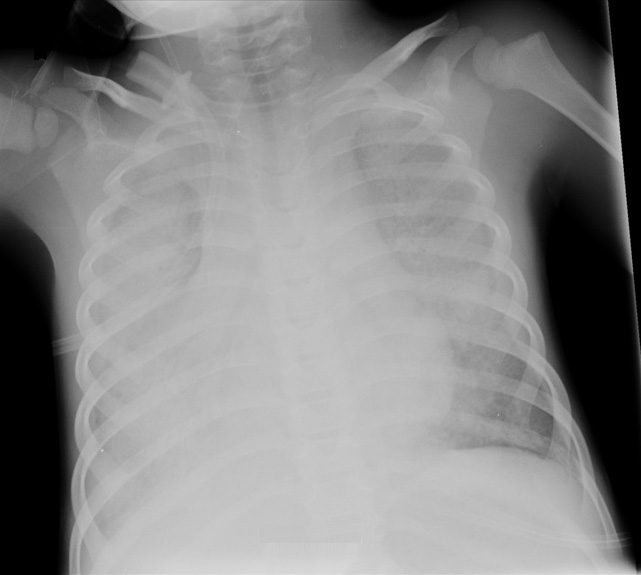

Respuesta correcta. En una radiografía simple resulta prácticamente imposible distinguir la sangre del líquido libre producto de un edema alveolar. En ambas situaciones resulta típica la imagen en “alas de mariposa”, debiendo utilizar la clínica asociada para orientar el diagnóstico.

La presencia de signos o síntomas de fallo cardiaco o shock de origen cardiogénico (hepatomegalia, hipotensión, edemas en miembros inferiores, soplos o latido hiperdinámico) orienta hacia un edema agudo de pulmón.

La tos con esputo sanguinolento, la hemoptisis o una anemización brusca en relación al aumento dificultad respiratoria podrían estar relacionados con un sangrado agudo.